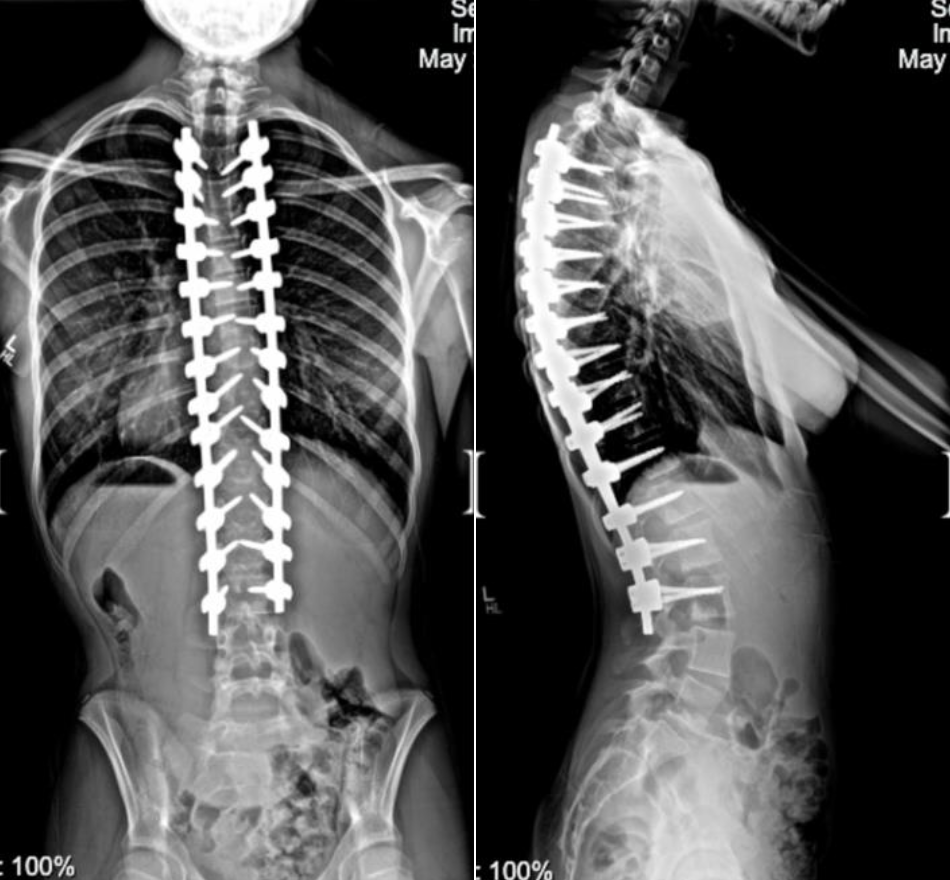

Below are before and after photos of two of our patients who underwent a posterior spinal fusion, one for scoliosis and one for kyphosis.

Kyphosis